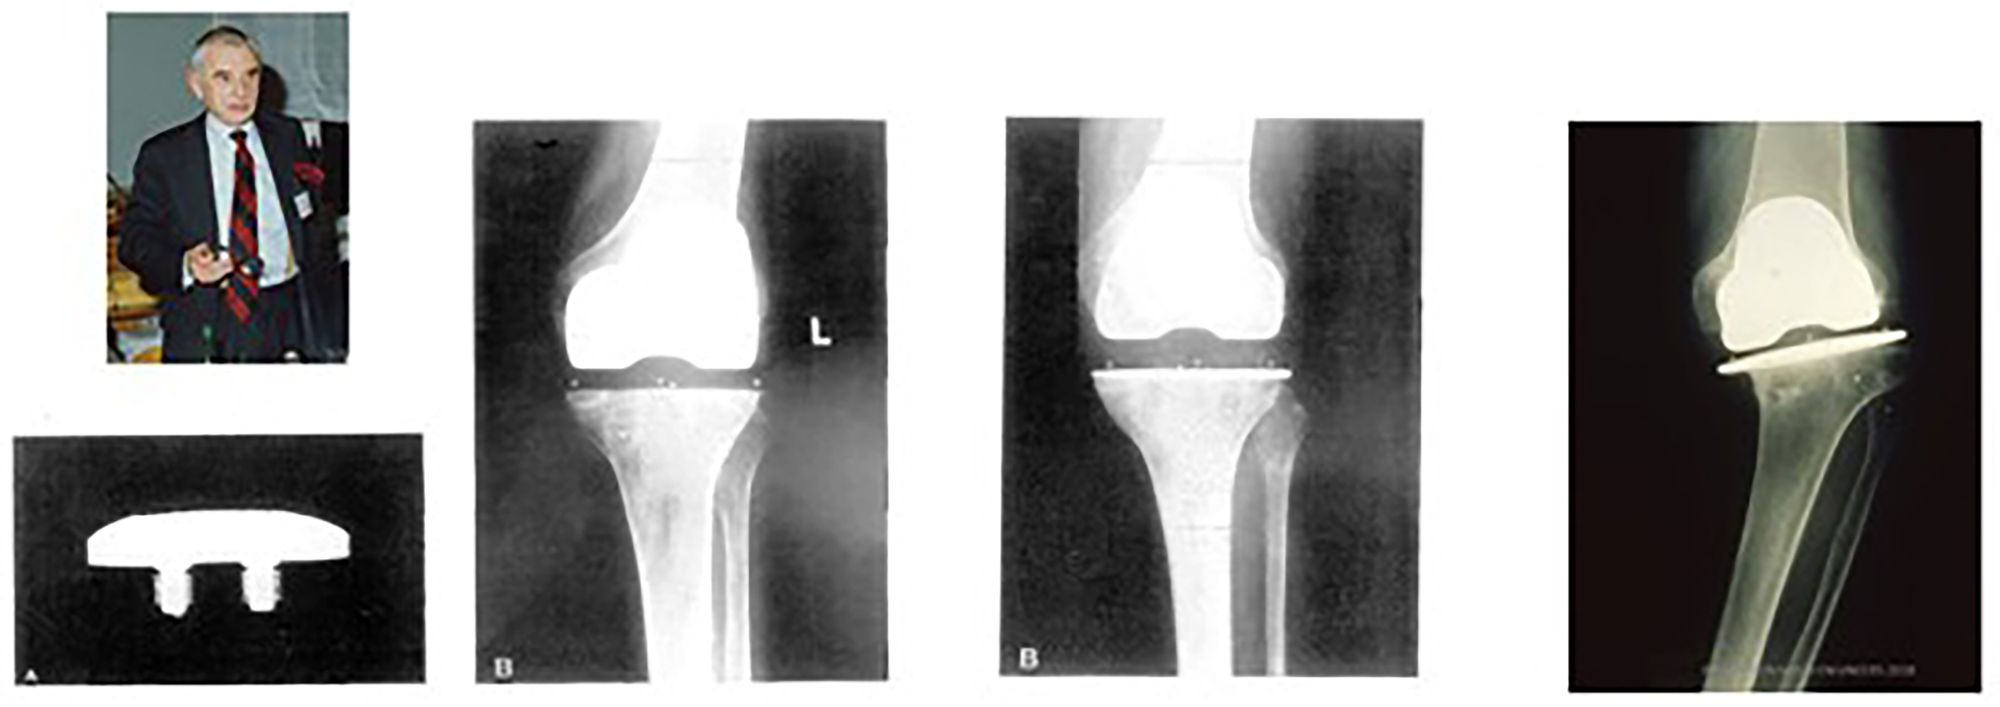

The 3 M Capital hip disaster brought to light several other failings besides the uptake of a poor design. In the UK, we had little idea of which patients had received these hips and no easy way of contacting them. The 3 M capital hip was the trigger for the NJR and ODEP for hips, but we all were aware of several types of joint replacement that not lived up to expectation and as surgeons there were many of us who had been demanding a registry for a considerable time (Fig 3).

The late Mike Freeman’s mark 1 knee worked well. The addition of a metal plate underneath the HDP Tibial component showed the unexpected consequence at 1 year.